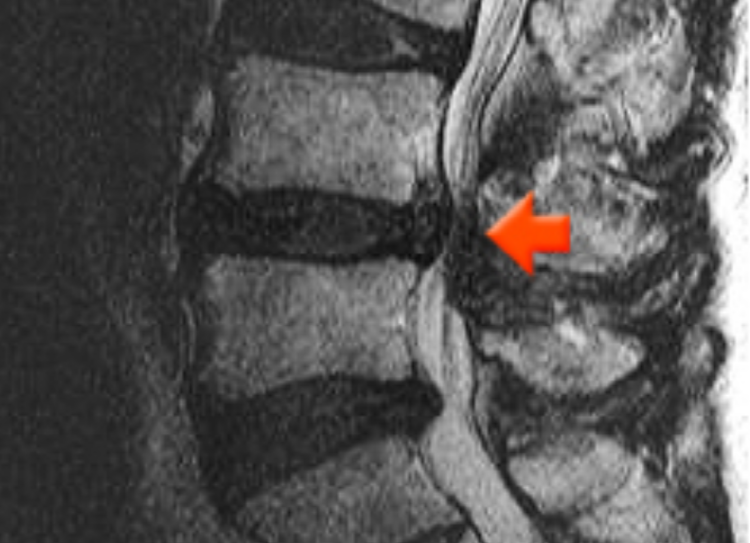

허리디스크 내부 손상이 일어나서 생긴 미세한 찢어짐은 MRI 촬영에서도 구분하기가 힘드니 허리디스크가 터지고 난 뒤에나 MRI로 확인할 수가 있습니다. 그래서 허리디스크 환자가 되지 않으려면 허리 삐끗했을때 무엇보다 바른 자세 관리가 중요합니다.

허리디스크 초기증상은 디스크성 요통이라고도 하며 허리 디스크 속의 수핵이 밖으로 탈출하지는 않았지만 디스크의 내부손상(주로 후방 섬유륜의 찢어짐)으로 인해 통증이 일어나는 것입니다. 다리 밑으로 통증이 이어지는 좌골신경통이 나타나지 않고 허리 주변부(허리, 엉덩이, 등아랫부분)만 아픈 것이 특징입니다.

디스크 후방섬유륜이 찢어지거나 종판에 손상이 있는 상태로, 디스크 내부의 손상부위에 염증이 생겨 통증이 발행함